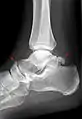

Lateral projection.[16]

BonePrevalence[17]

Sesamoid bones

Sesamoids at the metatarsophalangeal (MTP) joint of the great toeAlways present

Sesamoid of the second metatarsal0.4%

Sesamoid of the third metatarsal0.2%

Sesamoid of the fourth metatarsal0.1%

Sesamoids of the fifth metatarsal4.3%

Sesamoid of the interphalangeal (IP) joint of the great toe2–13%

Ossicles

Os trigonum (not visible in this dorsoplantar projection)7–25%

Os peroneumUp to 26%

Accessory navicular2–21%

Os intermetatarseum1–13%

Os supranaviculare, also called the talonavicular bone1.0–3.5%

Os calcaneus secundarium0.6–7%

Os supratalare0.2–2.4%

Os vesalianum0.1–1%

Os talotibiale 0.5%